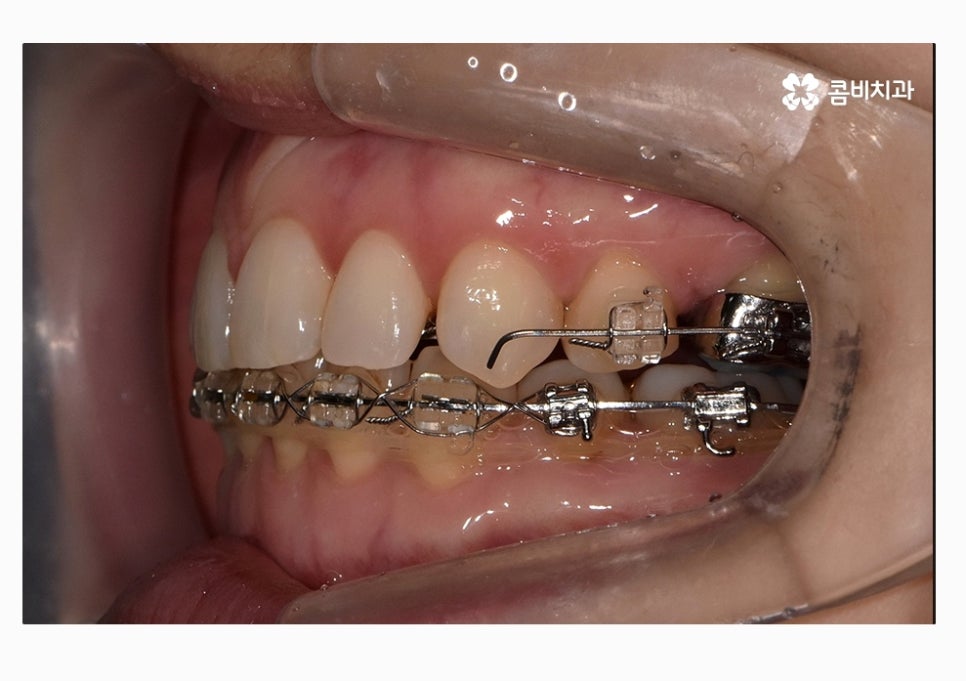

콤비교정은 윗니는 치아의 안쪽에 교정기를 부착하고

아랫니는 치아의 바깥쪽에 장치를 부착하는 방법으로

크게 웃지 않는다면 평소에는 잘 티가 안 나는

심미적으로 우수한 교정 방법이라고 할 수 있어요.

이번 케이스의 환자분의 경우에는 3급 부정교합과 절단교합을 치료하기 위해서

콤비교정을 시작하기 전에 발치를 먼저 진행하였는데

위 환자분의 경우에는 콤비교정의 치료 경과를 보면

아랫니가 정상교합이 되었고 치열도 보다 가지런하게

변화되고 있음을 알 수 있는데요.